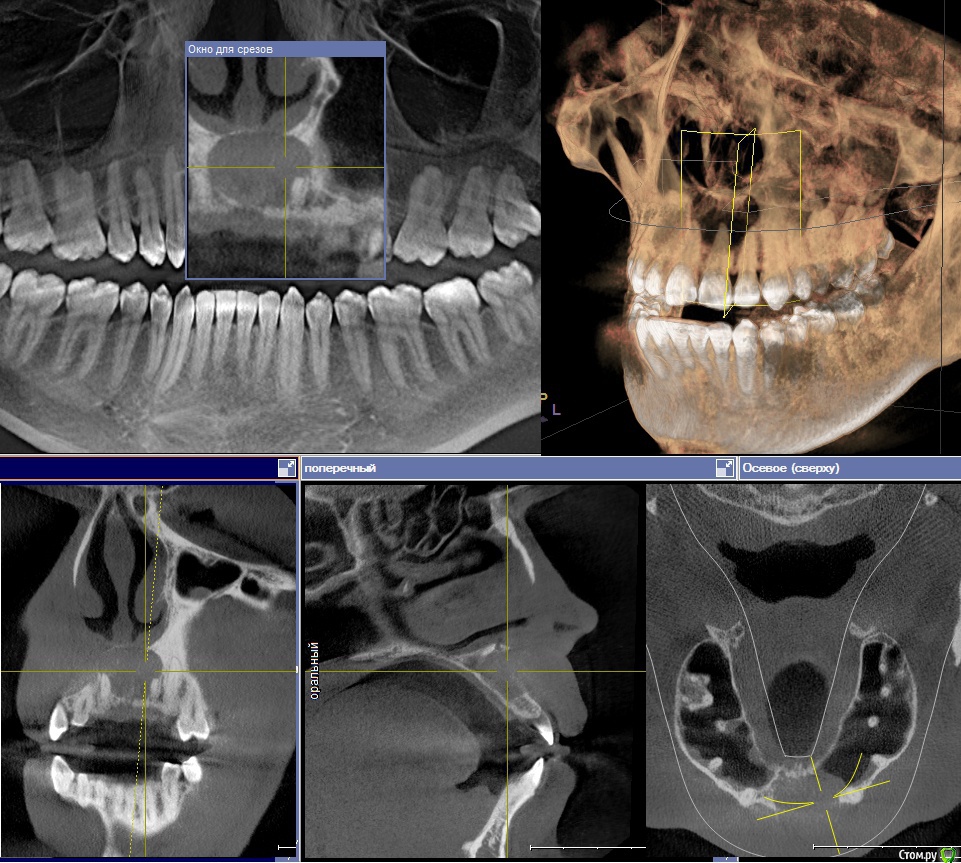

mike302459 Опубликовано 13 июня, 2018 Поделиться Опубликовано 13 июня, 2018 (изменено) Описание:Где-то полгода назад у зуба появилась сильная чувствительность, на еду, воду, не важно какой температуры. Это прошло за пару недельВ марте я нащупал языком некую припухлость, "шишка" на десне над передними зубами. С течением времени она заметно не изменялась.Примерно 20ого мая, начала воспаляться и пухнуть. Немного опухла губа, десны, и край десны "налез" до середины зуба.Далее где-то через неделю образовался свищ, над зубом 2.1, и начала вытекать белая субстанция, и янтарная жидкость из свища и между зубом и десной.Еще пару дней оттуда текло, потом всё зажило, отёк спал, шишка на десне осталась как в начале, в марте.Цвет одного зуба изменен - 2.1(уже давно).Всё это время каких то сильных болей не было, температуры не было. Потом пошёл в поликлинику, сделали КТ, не стали лечить, посоветовали врача, тот врач посоветовал еще врача.В последнем месте на словах предложили примерно такой план лечения. (С трудом это всё выяснил, диалог не задался, да и были неприятные моменты)" Сейчас сделаем разрез, промоем полость кисты, потом пойдешь в свою поликлинику пусть там запломбируют канал. Будешь промывать самостоятельно эту полость несколько месяцев, она будет зарастать. Но скорее всего всё не зарастёт, придешь на еще одну операцию" (Какую?)На бумаге потом написали так: Диагноз: Радикулярная киста зуба 2.1. Пациенту рекомендовано хирургическое лечение в объеме резекции корня зуба 2.1 + цистотомия.1. Эндодонтическое лечение зуба 2.1. Вопросы:1. Чтобы вы посоветовали по данной проблеме?И если возможно, то посоветуйте где в Москве можно этим заняться.2. И что сначала делать: резать кисту или пломбировать канал. Я читал мнения, что сначала запломбировать канал, как причину. Но вот откроют его, а оттуда же польётся содержимое кисты? прикрепляю скриншоты из программы со снимком. На втором немного изменил плоскость. Изменено 13 июня, 2018 пользователем mike302459 Ссылка на комментарий